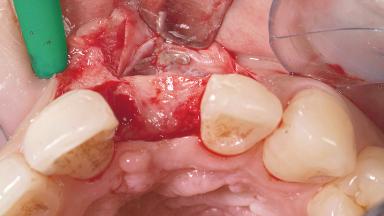

A 30-year-old female patient had lost tooth 21 and was referred to our clinic for consultation and treatment. Due to advanced apical infection, tooth 21 had been extracted two months earlier at another clinic and an acrylic-resin tooth had been bonded to the adjacent teeth. The patient desired implant treatment to avoid any damage to the adjacent natural teeth. While the patient had no history of any systemic disorder, she was a heavy smoker and exhibited medium to advanced periodontitis in the entire jaw. After the initial treatment to achieve a pocket probing depth of less than 4 mm and no bleeding on probing, a decrease in the height of the papillae mesial and distal to the extraction site and overall gingival recession were observed.

Bone Augmentation Horizontal|Staged

Augmentation Materials Autogenous chips|Membrane

Soft Tissue Grafting Simultaneous

Bone Volume Deficient horizontally, requiring prior grafting